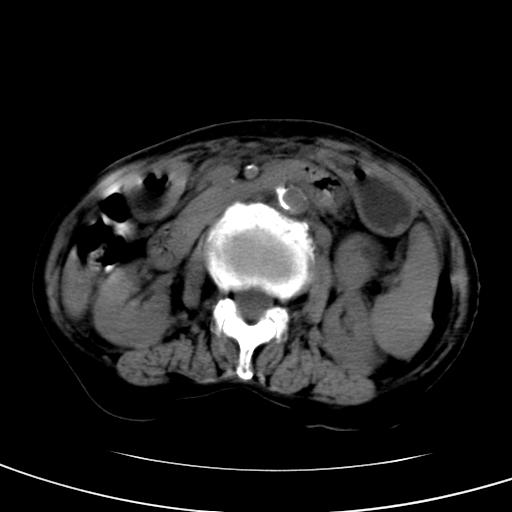

以下是引用wolft在2008-3-5 12:30:00的发言:[br]肝脏未见明显肿块影,但肝左叶增大,跨越腹中线到达脾胃前,且有一血管过去,考虑为先天变异:獭尾肝,胆囊为慢性胆囊炎急发,但胰腺头颈部有增大,密度不均匀,应该ct增强一下。

以下是引用zjzjr在2008-3-5 16:41:00的发言:[br]1.考虑慢性胰腺炎急性发作,建议增强除外占位性病变.[br]2.胆囊结石伴胆囊炎.[br]3.肝内胆管结石.